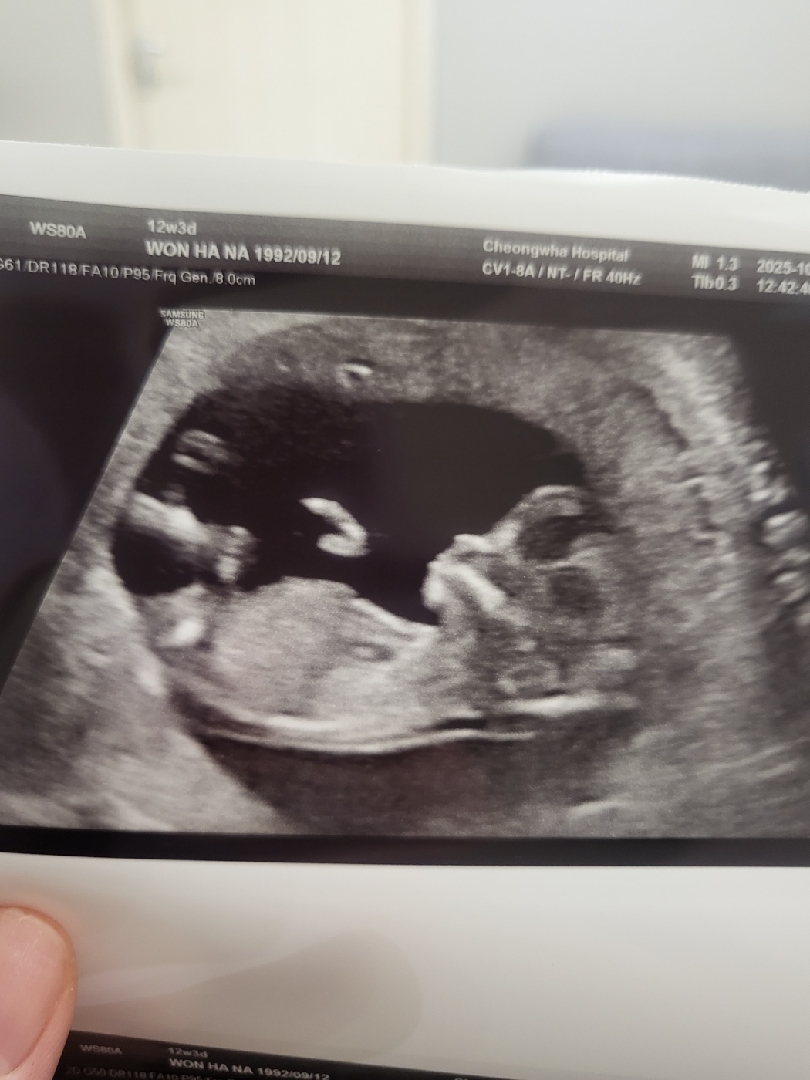

12주차 임산부입니다 각도법 봐주세요

니프티 검사하고 기다리는중인데 성별이 너무 궁금합니다 우리아이는 딸일까요 아들일까요